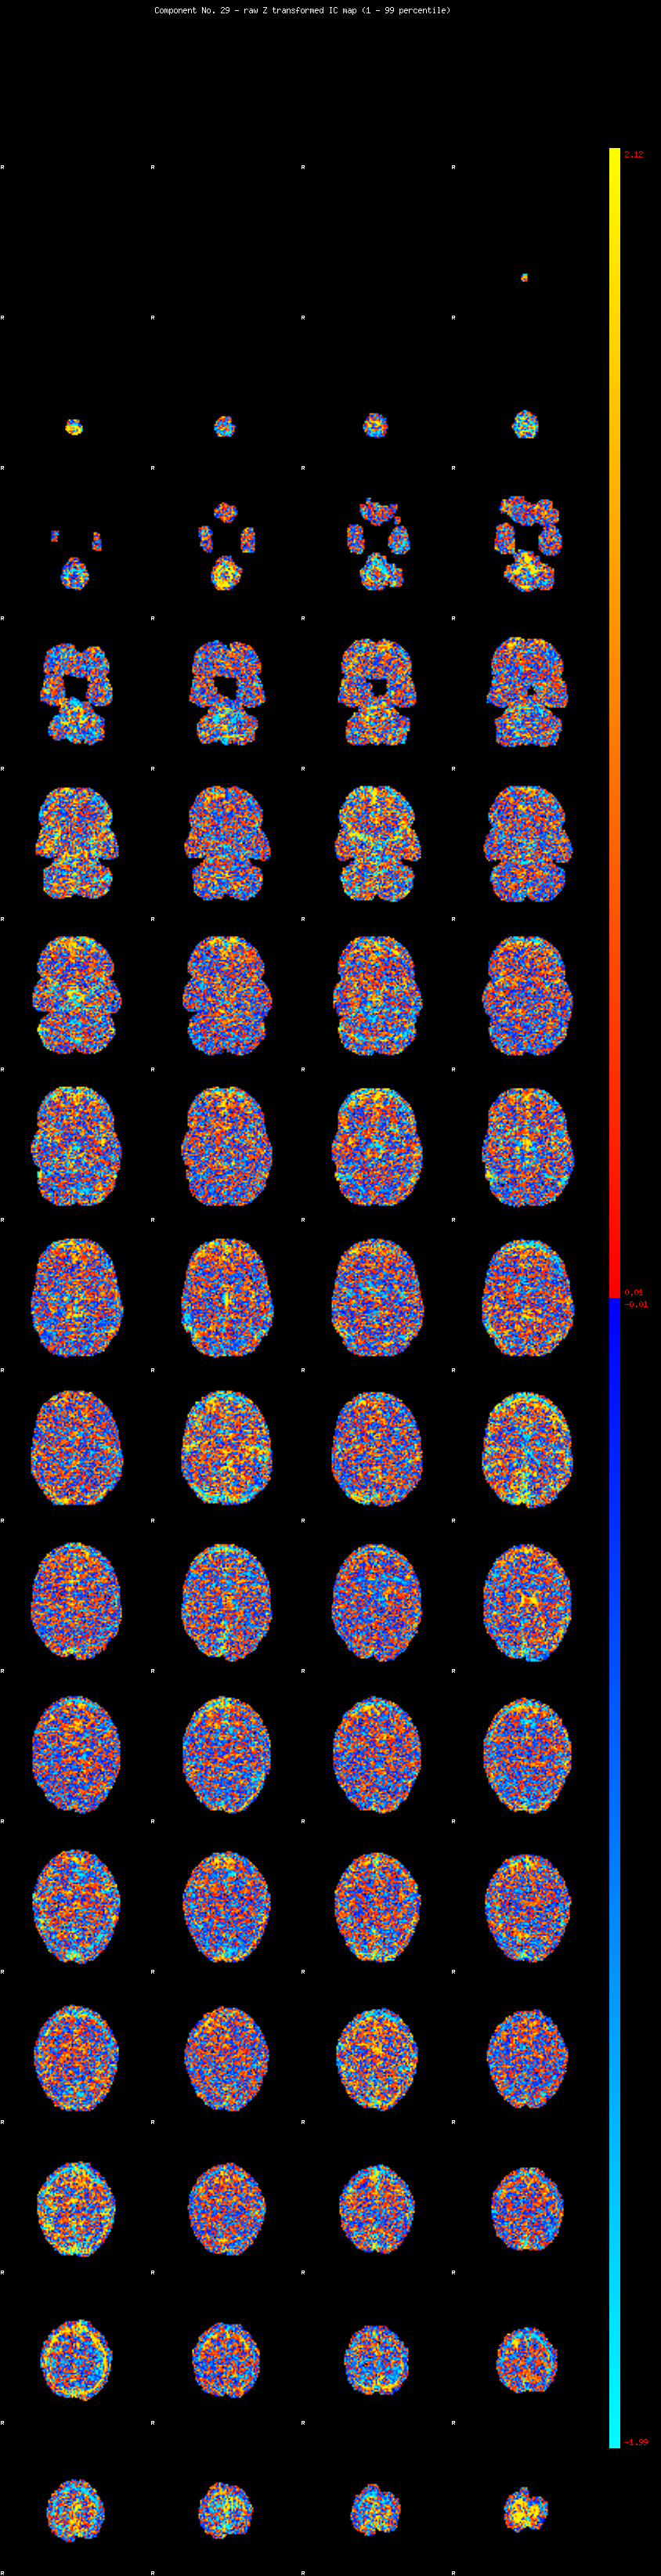

IC_29 Mixture Model fit

Means : -0.000000 2.578522 -2.420810

Vars : 1.000000 2.292167 1.820123

Prop. : 0.921880 0.044007 0.034112